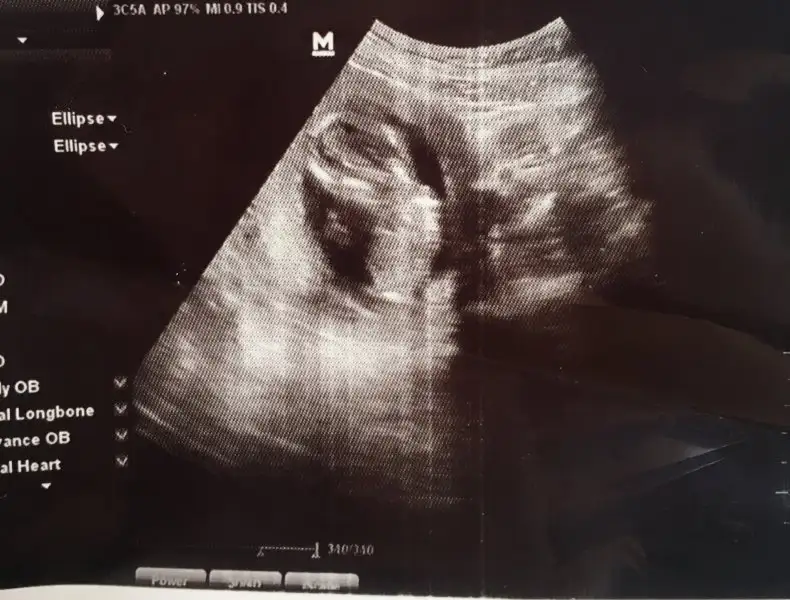

Canım ben pek anlayamıyorum cinsiyet meselesini ne olursa olsun hayırlısını diliyorum sizin içinBugün gittik 15.hafta ama göstermedi miniğim kendisini teyzeler neyseki herşey yolunda ve sağlıklıyız :) yorum bekliyoruz :)

Eki Görüntüle 2136158